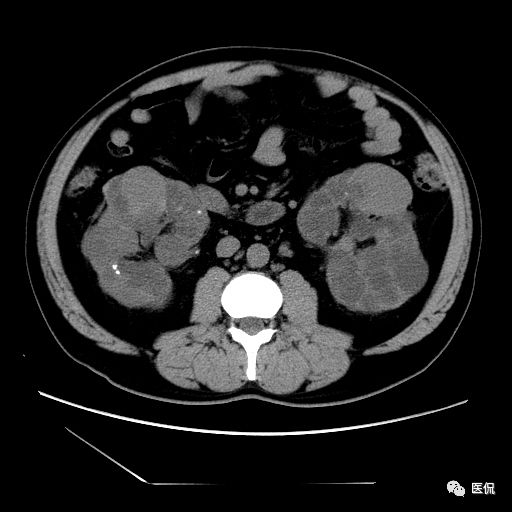

双肾实质可见多发囊性密度灶,其内密度不均匀,并可见钙化灶,增强扫描未见明显强化灶。肾周脂肪间隙清晰,与邻近组织分界清楚。

多囊肾的 CT 表现主要表现为双肾增大,轮廓光滑或有分叶,肾实质内多个大小不等的囊肿呈蜂窝状,多呈水样低密度,增强扫描囊肿本身无强化,而囊肿间正常肾组织增强,对比明显。当囊肿张力过高,使囊壁上毛细血管牵拉破裂出血时,表现为囊肿内稍高密度影,随访CT 值减低。囊壁钙化,表现为点线状高密度影像,随访CT值无变化。有文献报道约 30%病例可并发多囊肝或多囊胰。